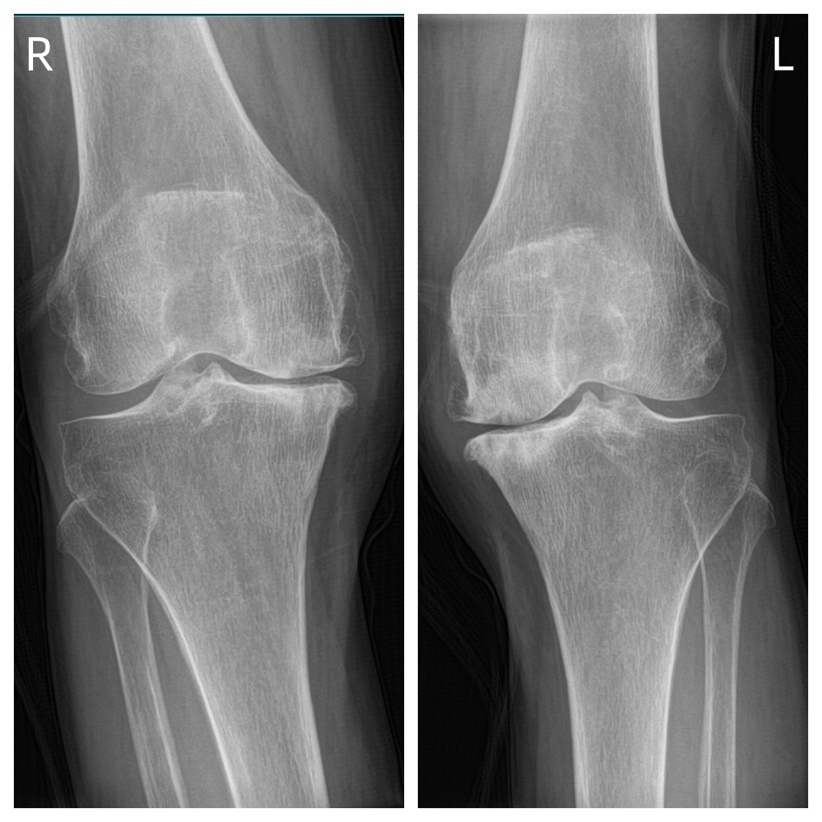

▲x 线检查可见关节间隙变窄,软骨下骨硬化,囊性变,关节边缘骨赘形成,伴有骨质疏松和软组织肿胀